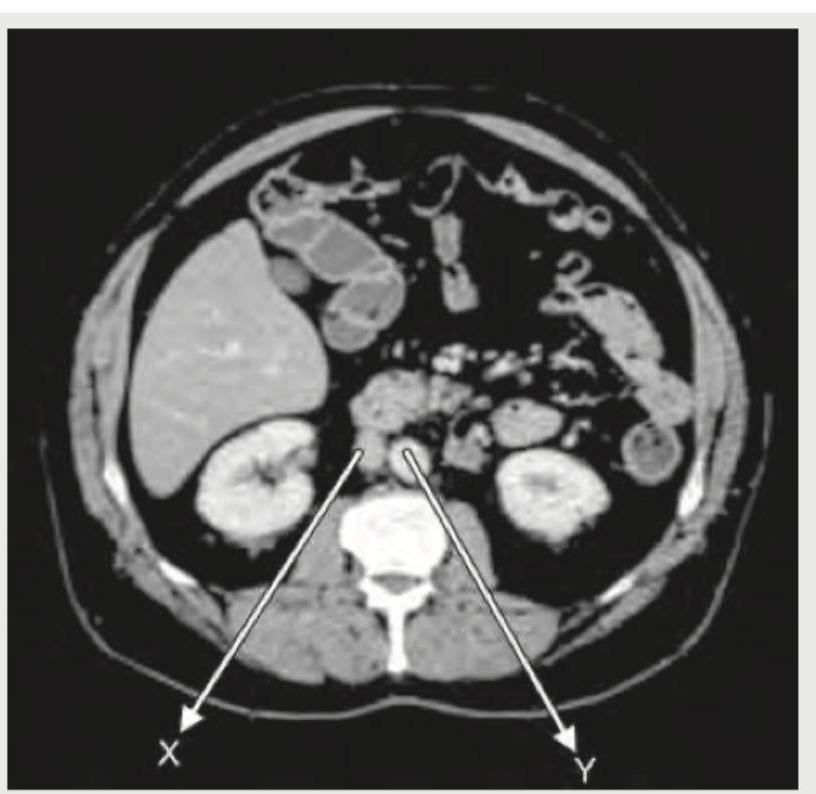

The given CT abdomen shows:

Explanation: ***X = Aorta: Y = Inferior vena cava*** - On a typical axial CT image, the **aorta (X)** is usually located to the **left and slightly posterior** of the inferior vena cava. It also has a **thicker, more defined wall** due to its muscular nature and higher pressure. - The **inferior vena cava (Y)** is positioned to the **right and anterior** to the aorta. It typically appears with a **thinner and more variable wall** as it is a low-pressure vessel. *X = Inferior vena cava : Y = Aorta* - This option incorrectly identifies the vessels. The **IVC** (Inferior Vena Cava) is generally located **to the right** of the vertebral body, while the **aorta** is typically found **to the left**. - The **aorta has thicker walls** and maintains a more circular shape, whereas the IVC's shape can distort depending on respiration and intravascular volume. *X = Aorta : Y = Superior mesenteric artery* - While X correctly identifies the aorta, Y incorrectly identifies the **superior mesenteric artery (SMA)**. The SMA is a smaller arterial branch that typically arises from the aorta more anteriorly and inferiorly, and is not the large vessel indicated by Y in this image. - The vessel at Y is too large and the wrong anatomical position to be the SMA, which is usually seen more anteriorly, often surrounded by mesenteric fat. *X = Superior mesenteric artery: Y = Aorta* - This option is incorrect because **X is too large** and in the wrong anatomical position to be the superior mesenteric artery. The SMA is a branch of the aorta, not the main vessel itself at this central location. - Y is also incorrectly identified as the aorta. As explained earlier, the **aorta is typically to the left** of the vertebral body and has a thicker wall, fitting the description for X.